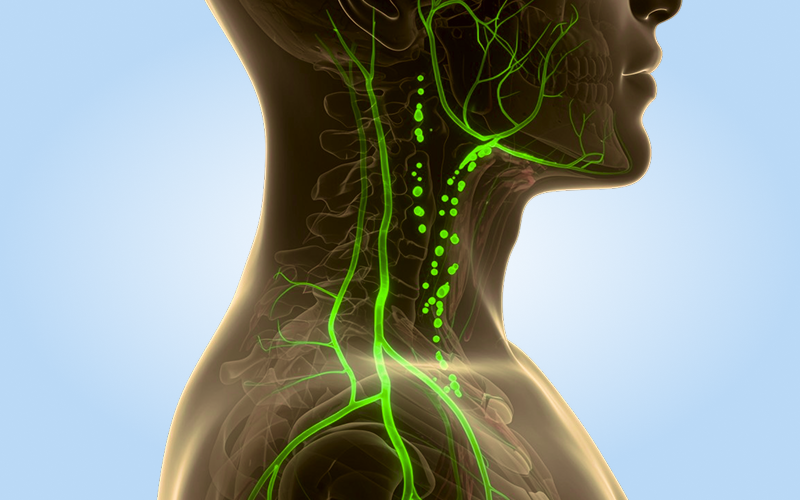

Флуоресцентная лимфография (ICG-лимфография) — это метод оценки лимфатического дренажа, который позволяет определить наличие, локализацию и причину нарушений оттока лимфы. Исследование показывает состояние сосудистой сети в режиме реального времени и считается неотъемлемой частью современной диагностики лимфостаза.

Для выявления заболеваний лимфатической системы применяют разные аппаратные процедуры: ультразвуковое сканирование, рентгенконтрастную и магнитно-резонансную лимфографию. Каждая из них имеет высокую диагностическую ценность, но флуоресцентная методика обладает рядом уникальных преимуществ:

- визуализирует застой лимфы на ранней стадии даже при отсутствии характерных внешних симптомов;

- показывает все аномалии сосудистой сети, включая мелкие дефекты, которые остаются незамеченными при других исследованиях;

- позволяет составить точную карту лимфатических сосудов для подготовки к хирургическим вмешательствам;